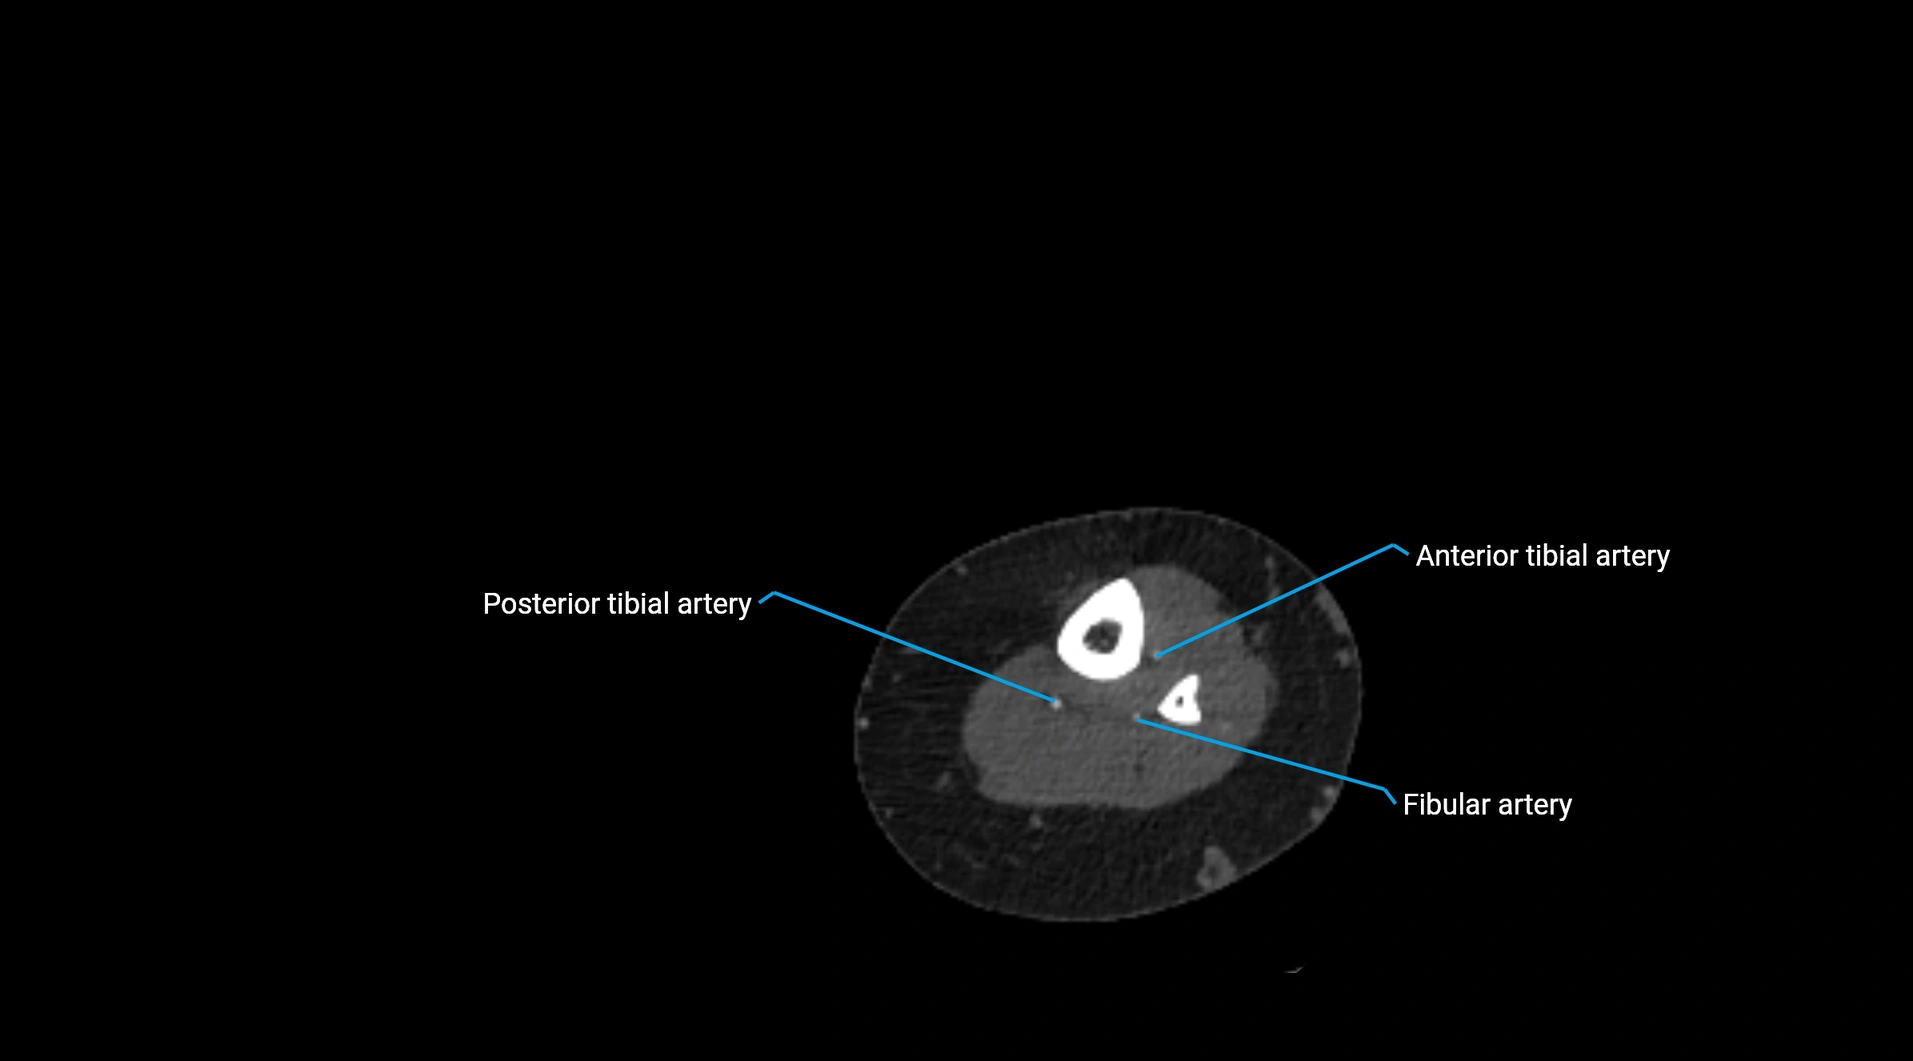

CT Appearance

Non-contrast CT:

• Appears as a tubular soft tissue structure anterior to vertebral bodies

• Calcified atherosclerotic plaques appear as hyperdense foci along the wall

• Useful for screening abdominal aortic aneurysm (AAA) size and mural calcification

Contrast-enhanced CT (CTA):

• Gold standard for abdominal aortic imaging

• Provides excellent detail of lumen, wall, aneurysm, thrombus, and branch vessels

• Multiplanar and 3D reconstructions help in aneurysm measurement, stent graft planning, and dissection evaluation

• Detects acute rupture, traumatic injury, or occlusion with high sensitivity